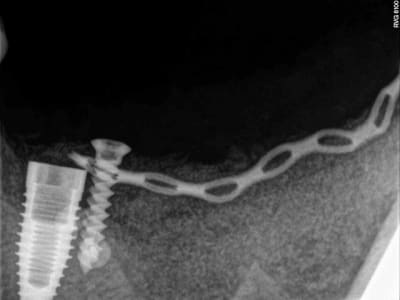

j'en viens maintenant au système FAST de Joseph.

1- les vis et la chaine titane adaptée aux vis.

(pour expliquer: ce système permet de maintenir la chaîne en l'air par sa tête.)

4-5-6-7 sciage de la mesh titane et positionnement in situ d'un bout à l'autre de l'arcade.

7 les radios post-op